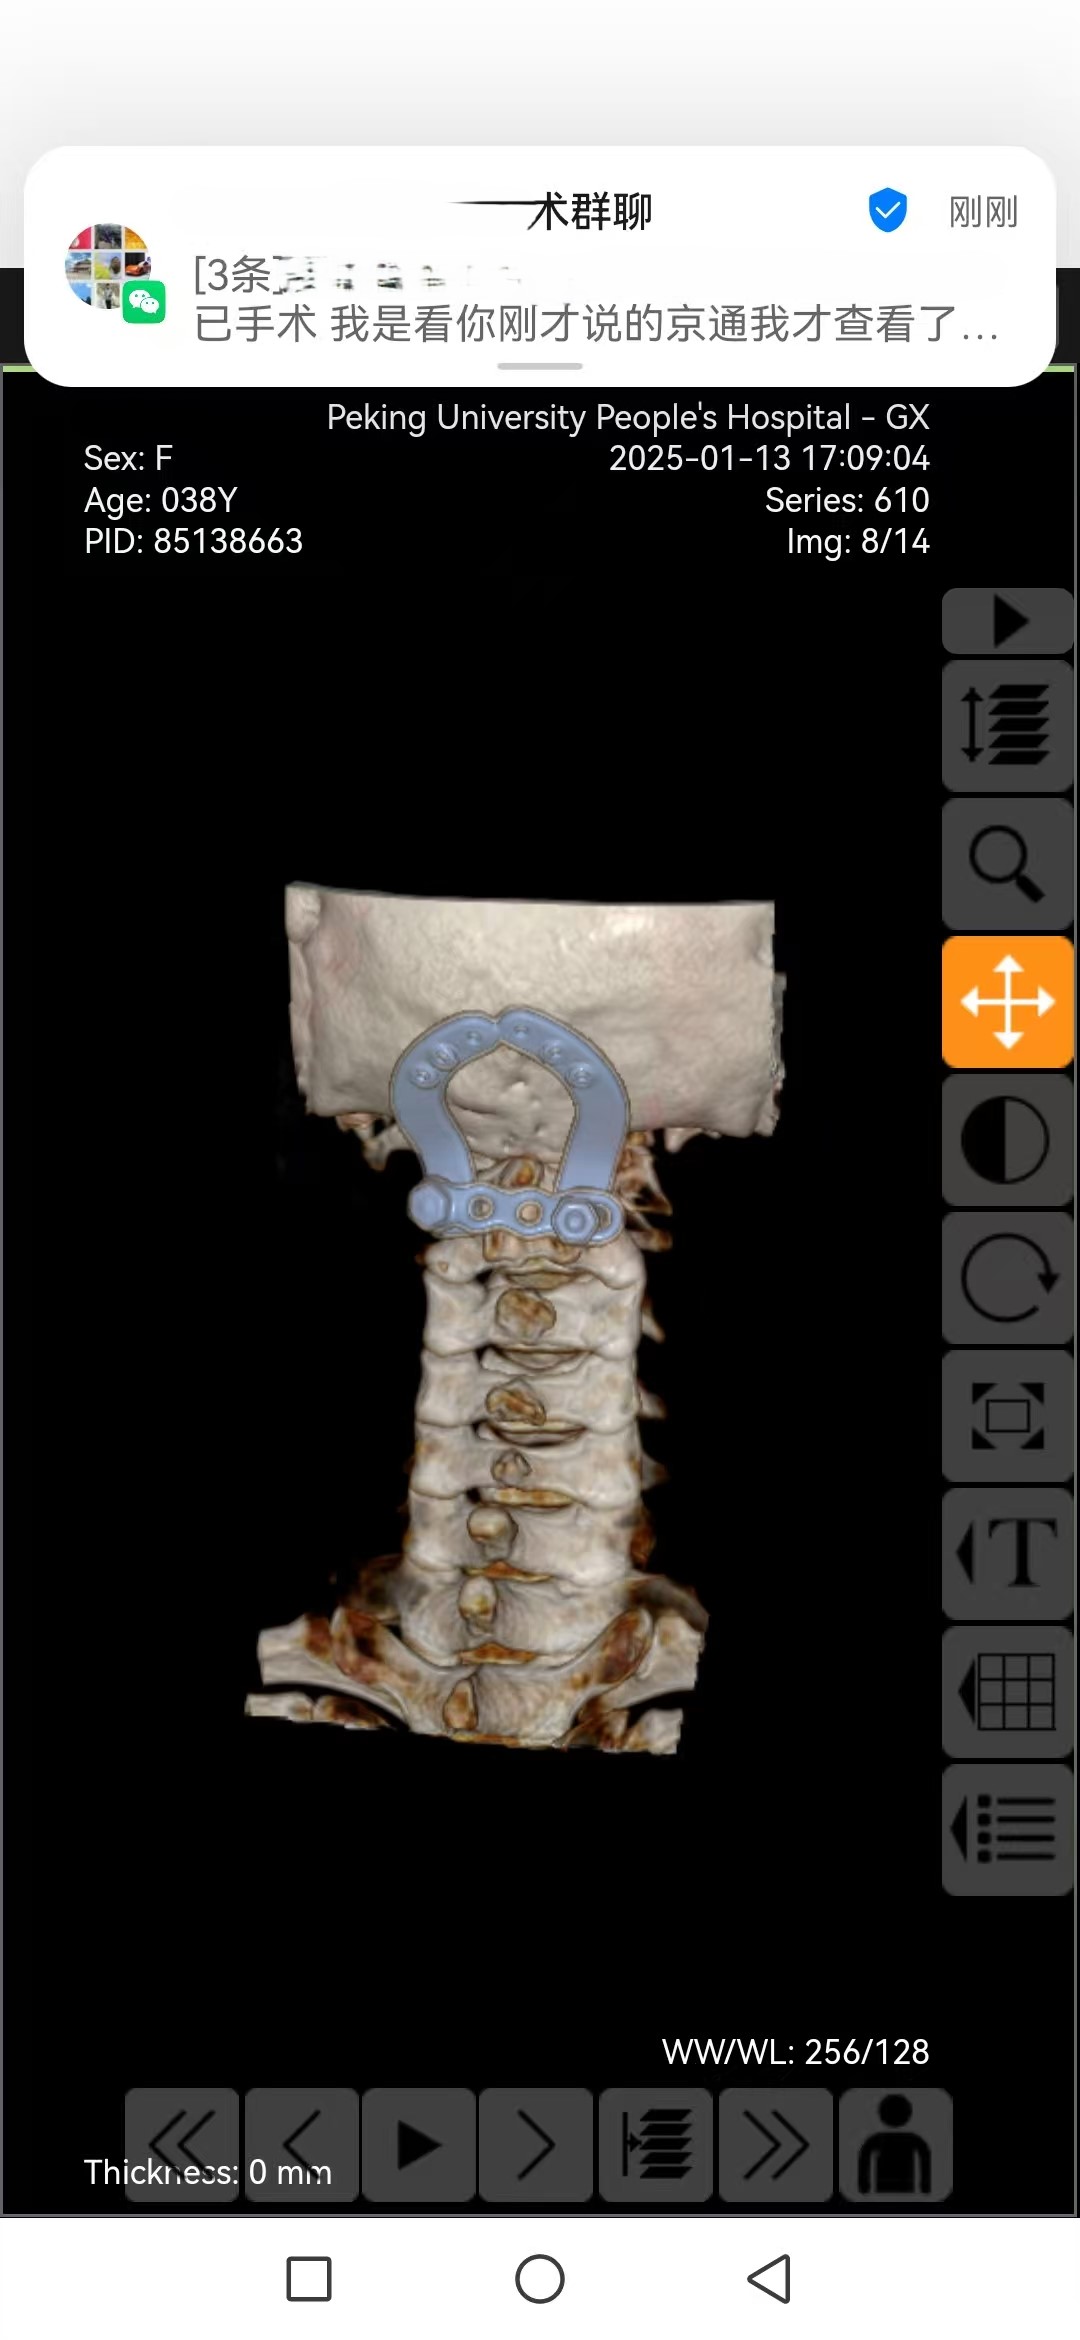

• 日期:2025.01.09

• 医院:人民医院

• 主刀:王超

• 术后影像: